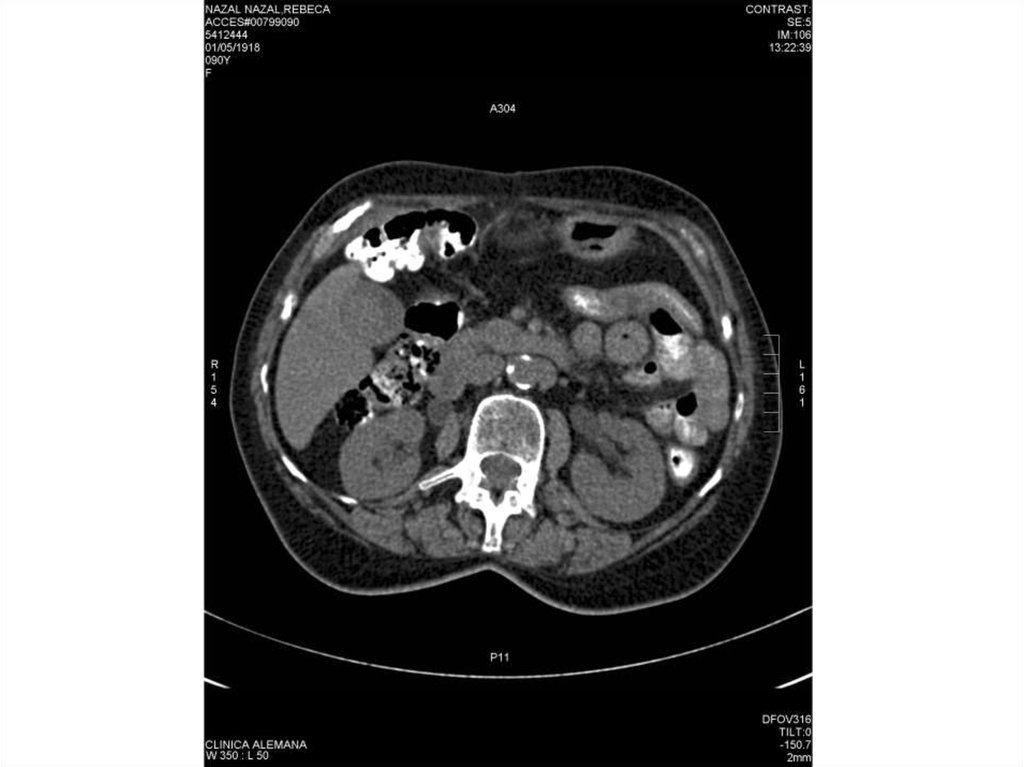

Специальные исследования

Эмфизематозный холецистит